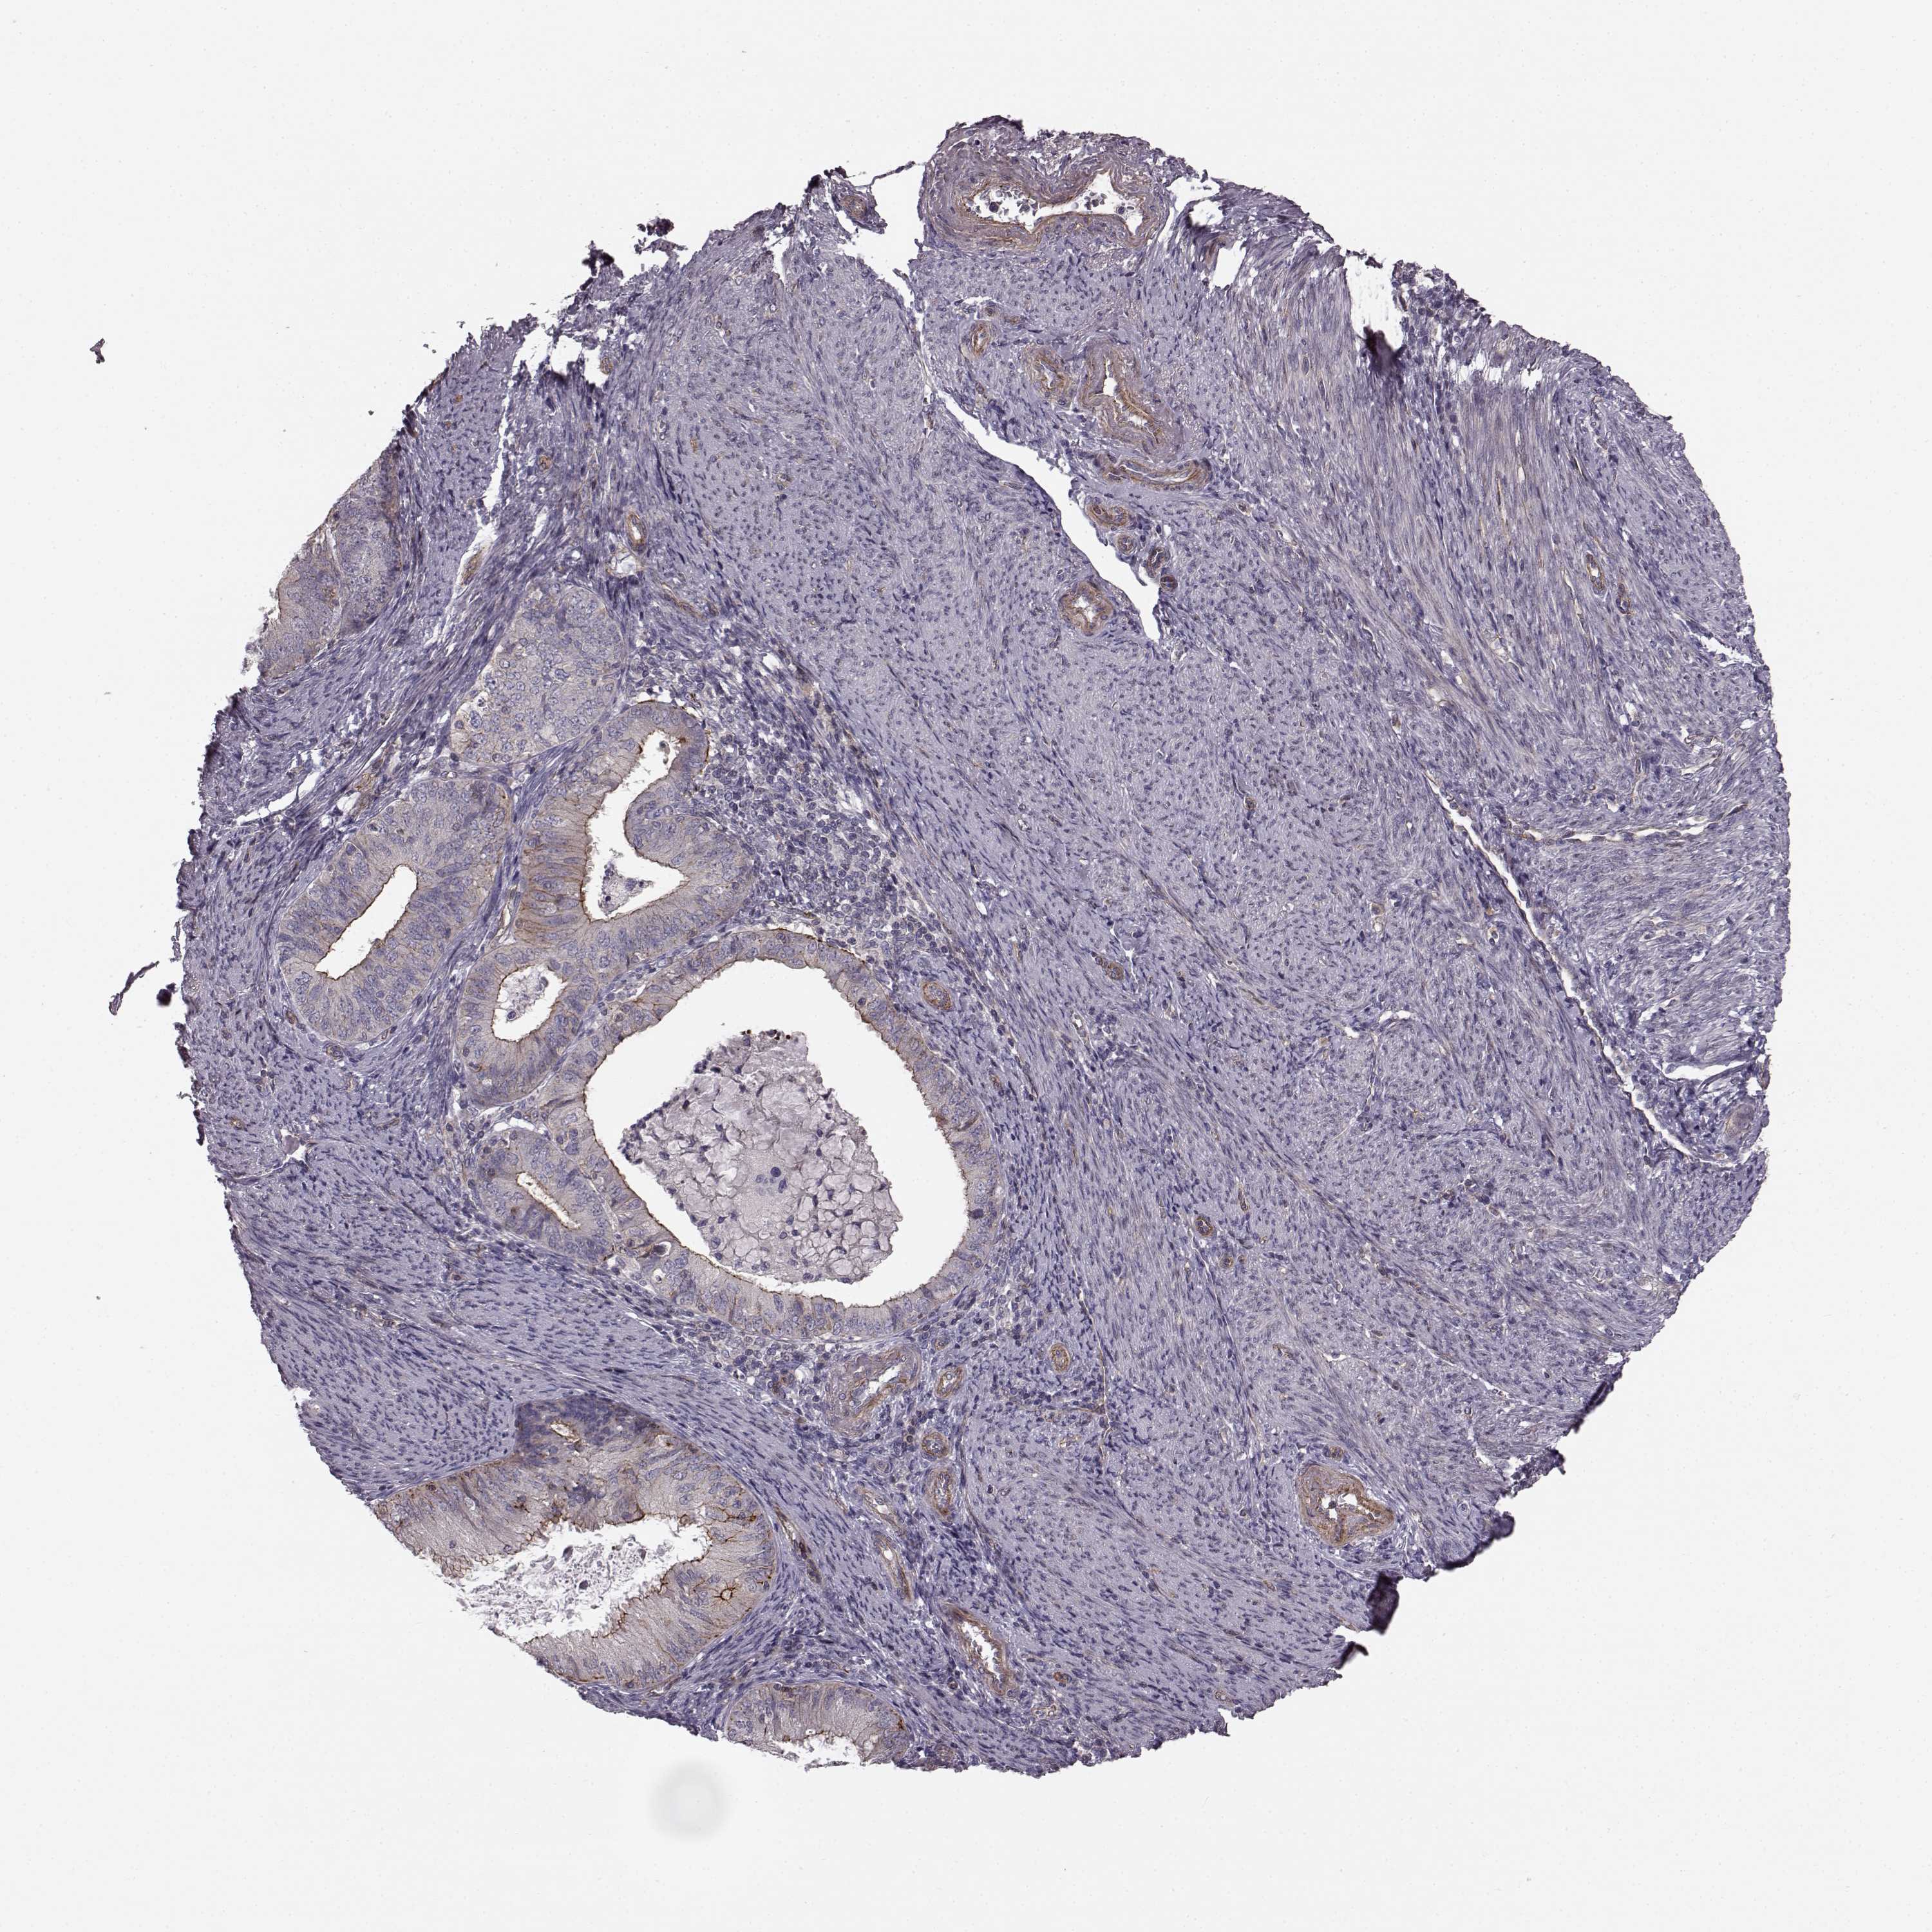

ENDOMETRIAL CANCER - Protein expressioni

A mouse-over function shows sample information and annotation data. Click on an image to view it in a full screen mode. Samples can be filtered based on level of antibody staining by selecting one or several of the following categories: high, medium, low and not detected. The assay and annotation is described here.

Note that samples used for immunohistochemistry by the Human Protein Atlas do not correspond to samples in the TCGA dataset.

Antibody stainingi

Antibody staining in the annotated cell types in the current human tissue is reported as not detected, low, medium, or high, based on conventional immunohistochemistry profiling in selected tissues. This score is based on the combination of the staining intensity and fraction of stained cells.

Each image is clickable and will lead to virtual microscopy that enables deeper exploration of all samples and also displays staining intensity scores, fraction scores and subcellular localization as well as patient and tissue information for each sample.

Antibody HPA067812

Antibody HPA071461

Staining

High

Medium

Low

Not detected

Intensity

Strong

Moderate

Weak

Negative

Quantity

>75%

75%-25%

<25%

None

Location

Nuclear

Cytoplasmic/membranous

Cytoplasmic/membranous,nuclear

Adenocarcinoma, NOS